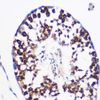

PGES / PTGES Rabbit Polyclonal (N-Terminus) Antibody

| Applications | IHC |